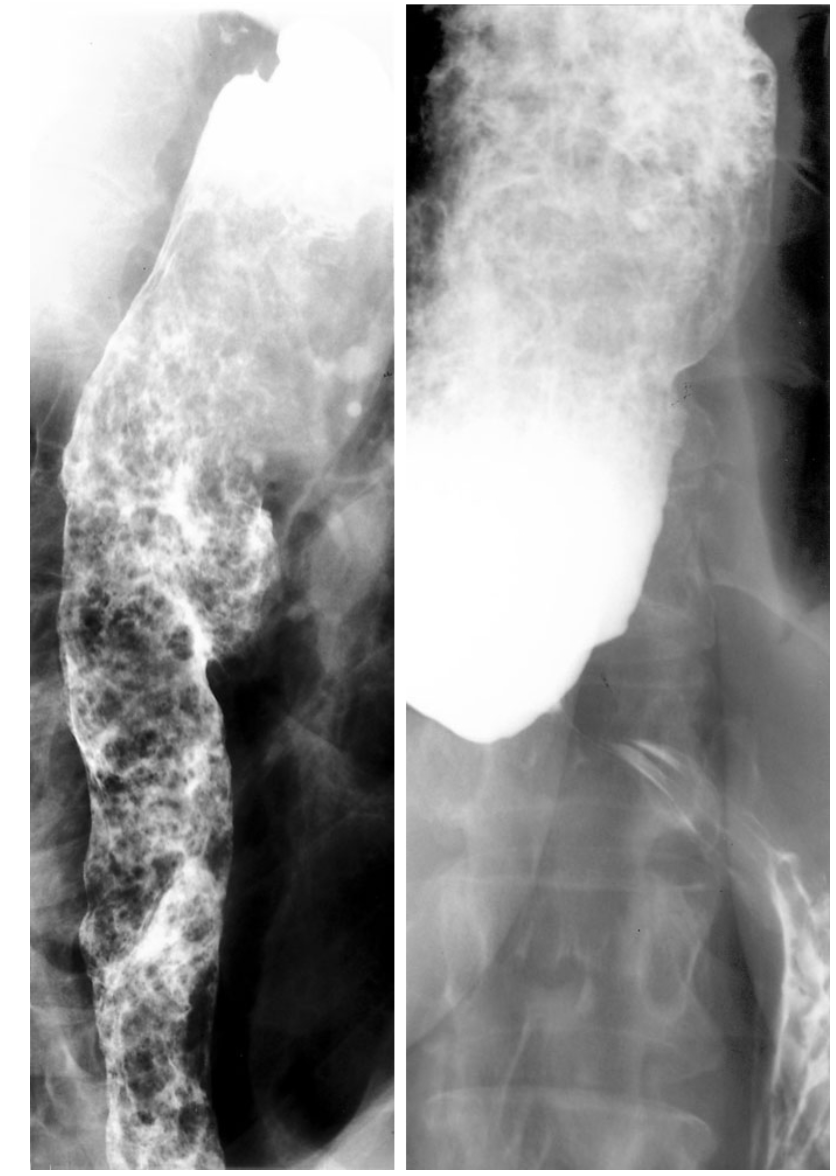

Take a look at this scan, what does it show and what is the most likley diagnosis?

Barium swallow.

There is tight, smooth narrowing noted of the lower oesophagus, which is dilated proximally and full of food residue.

This is in keeping with achalasia of the oesophagus.